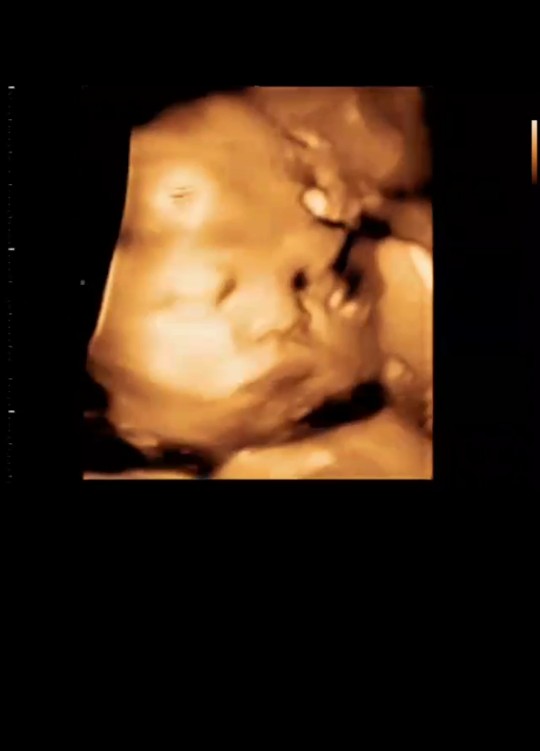

ขอดูรูปลูกๆตอนซาวด์แต่ละบ้านหน่อยค้าาคุณแม่ บ้านนี้พึ่งไปเมื่อวานได้ลูกผู้ชายสมใจอิพ่อเขาเลย ?

ซาวด์ตอน24สัปดาห์ค่ะ ลูกชายค่ะ